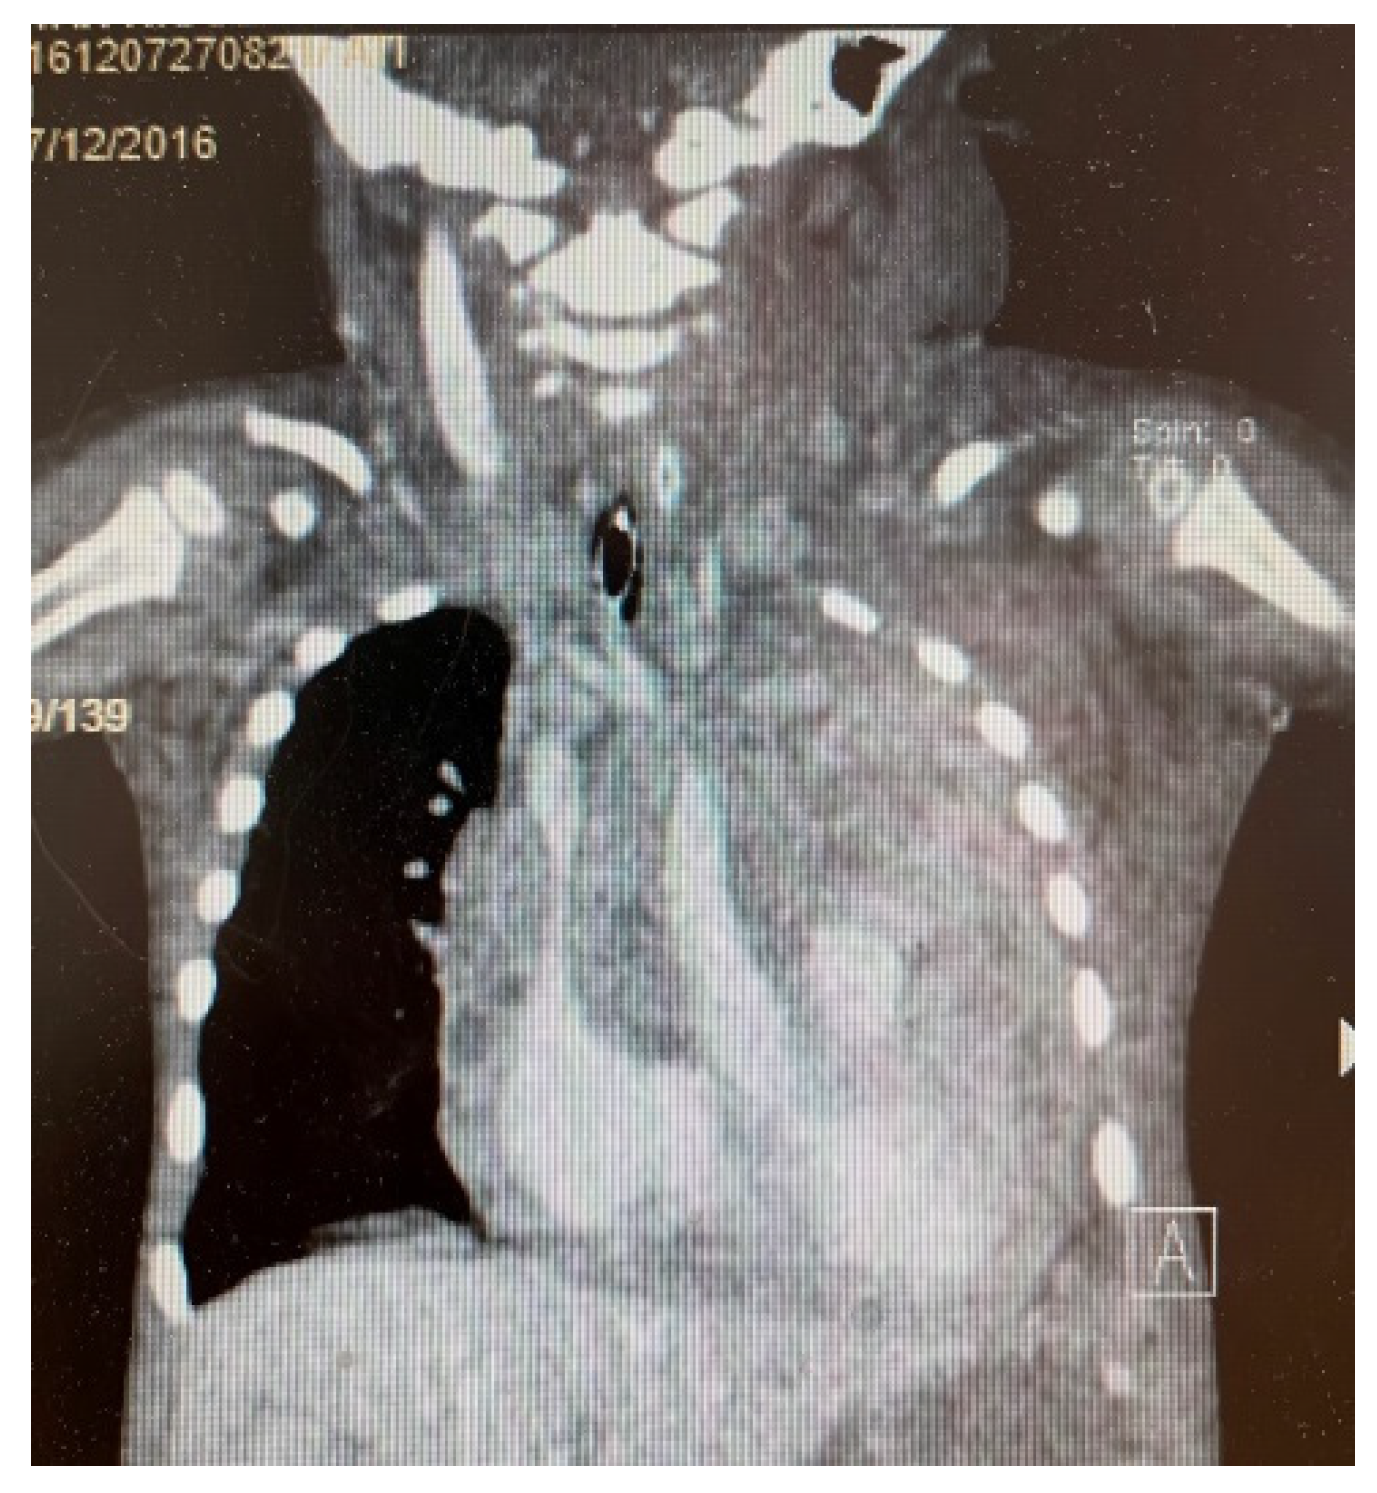

3. Results